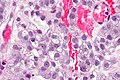

Micro

The sections show a tumour with a papillary cystic architecture that is composed of moderately atypical monomorphic cells with moderate pale grey cytoplasm. Focal cytoplasmic clearing is present. Hobnailing is present focally. The nucleoli are not prominent.